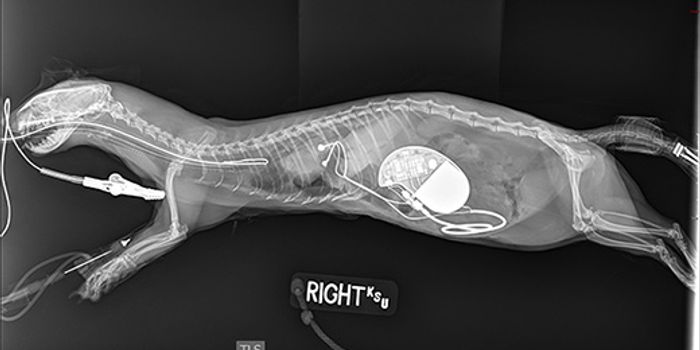

FEB 10, 2017Plants & AnimalsKansas State University surgeons had the rare opportunity to surgically-implant a one-of-a-kind pacemaker into a ferret ...

-